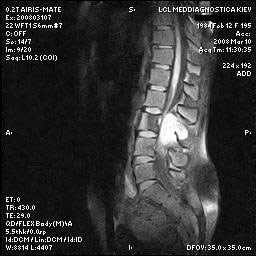

Спинальна магнітно-резонансна томографія (МРТ). Замість радіаційного випромінювання в МРТ використовуються потужні магнітні і радіохвилі для отримання зображення поперечного перерізу хребта. МРТ чітко відображає спинний мозок і нерви і забезпечує краще зображення пухлин кісток, ніж комп'ютерна томографія (КТ). Вам можуть ввести в вену кисті або передпліччя контрастну речовину, яка висвітлює деякі пухлини. Крім цього, використовують сканери з високою інтенсивністю сигналу для виявлення невеликих пухлин, які можна не помітити.